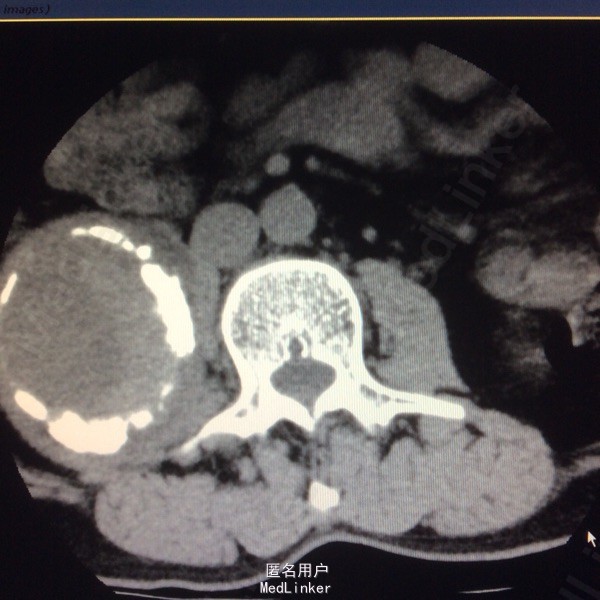

患者双下肢无明显浅感觉减退,肌力V级,肌张力不高,二便控制满意,病理征阴性。 腰椎核磁:腰1-4椎体右侧右肾下方团块状占位,大小约8#⃣6.8Cm,等T1长T2信号 腰椎Ct:占位周围见弧形钙化灶